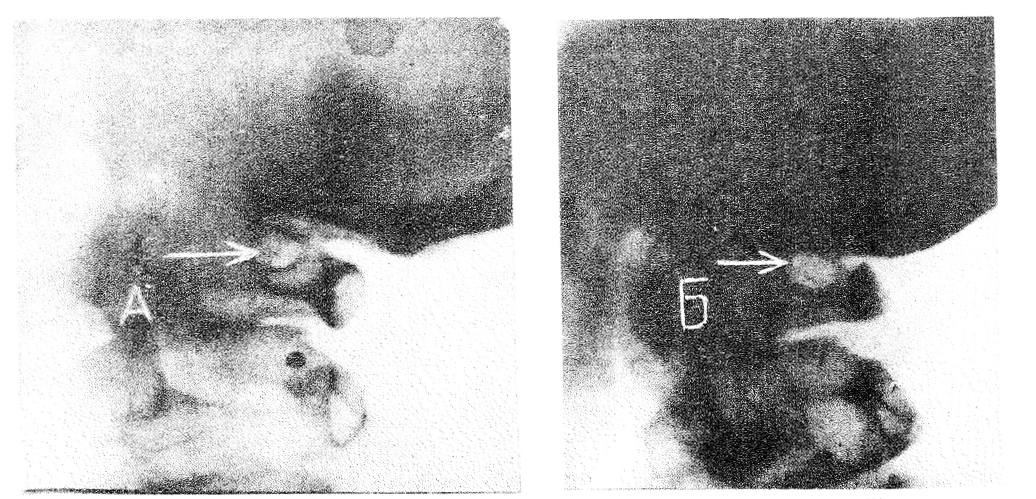

На рентгенограмме шейного отдела позвоночника в боковой проекции выявляется аномалия Киммерле в форме полного костного кольца (рис. А).

На рентгенограмме шейного отдела определяется аномалия Киммерле в форме полного костного кольца (рис. Б).

Аномалия Киммерле в форме замкнутого кольца у матери (А) и дочери (Б). Стрелкой указано костное кольцо